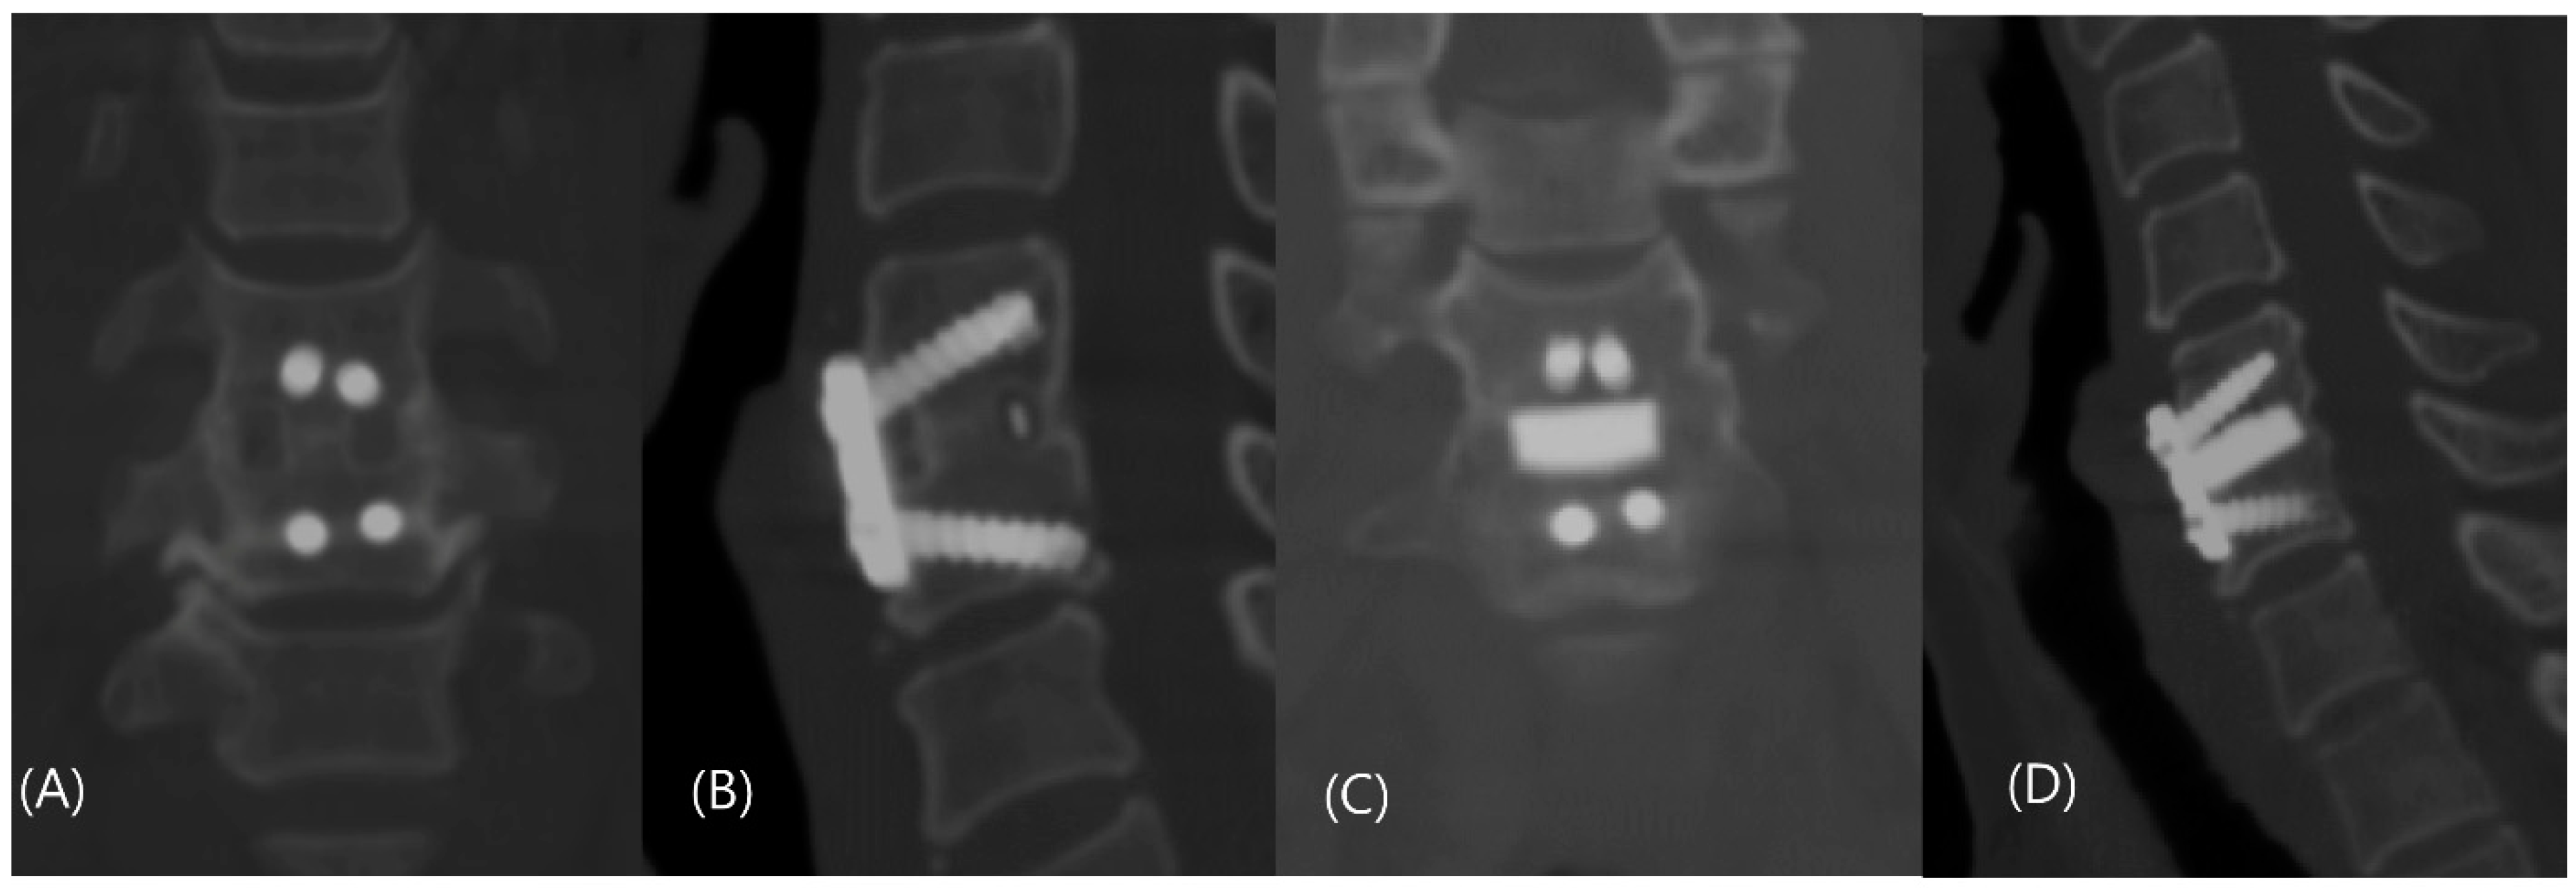

2.3. Interventions: Anterior Cervical Discectomy and Fusion